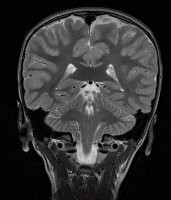

3. "Судя по всему, в мозге моего сына есть маленький мальчик. И это не фотошоп"